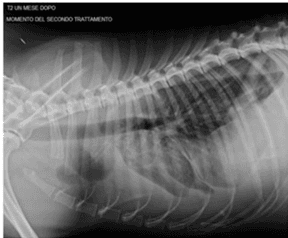

Case Report: Microfragmented Adipose Tissue Drug Delivery in Canine Mesothelioma: A Case Report on Safety, Feasibility, and Clinical Findings

Offer Zeira, Erica Ghezzi, Letizia Pettinari, Valentina Re, Davide M. Lupi, Silvia L. Benali, Simone Borgonovo, Giulio Alessandri, Francesco Petrella, Rita Paroni, Michele Dei Cas, Carlo Tremolada, Valentina Coccè, Augusto Pessina, Frontiers in Veterinary Science, 2021